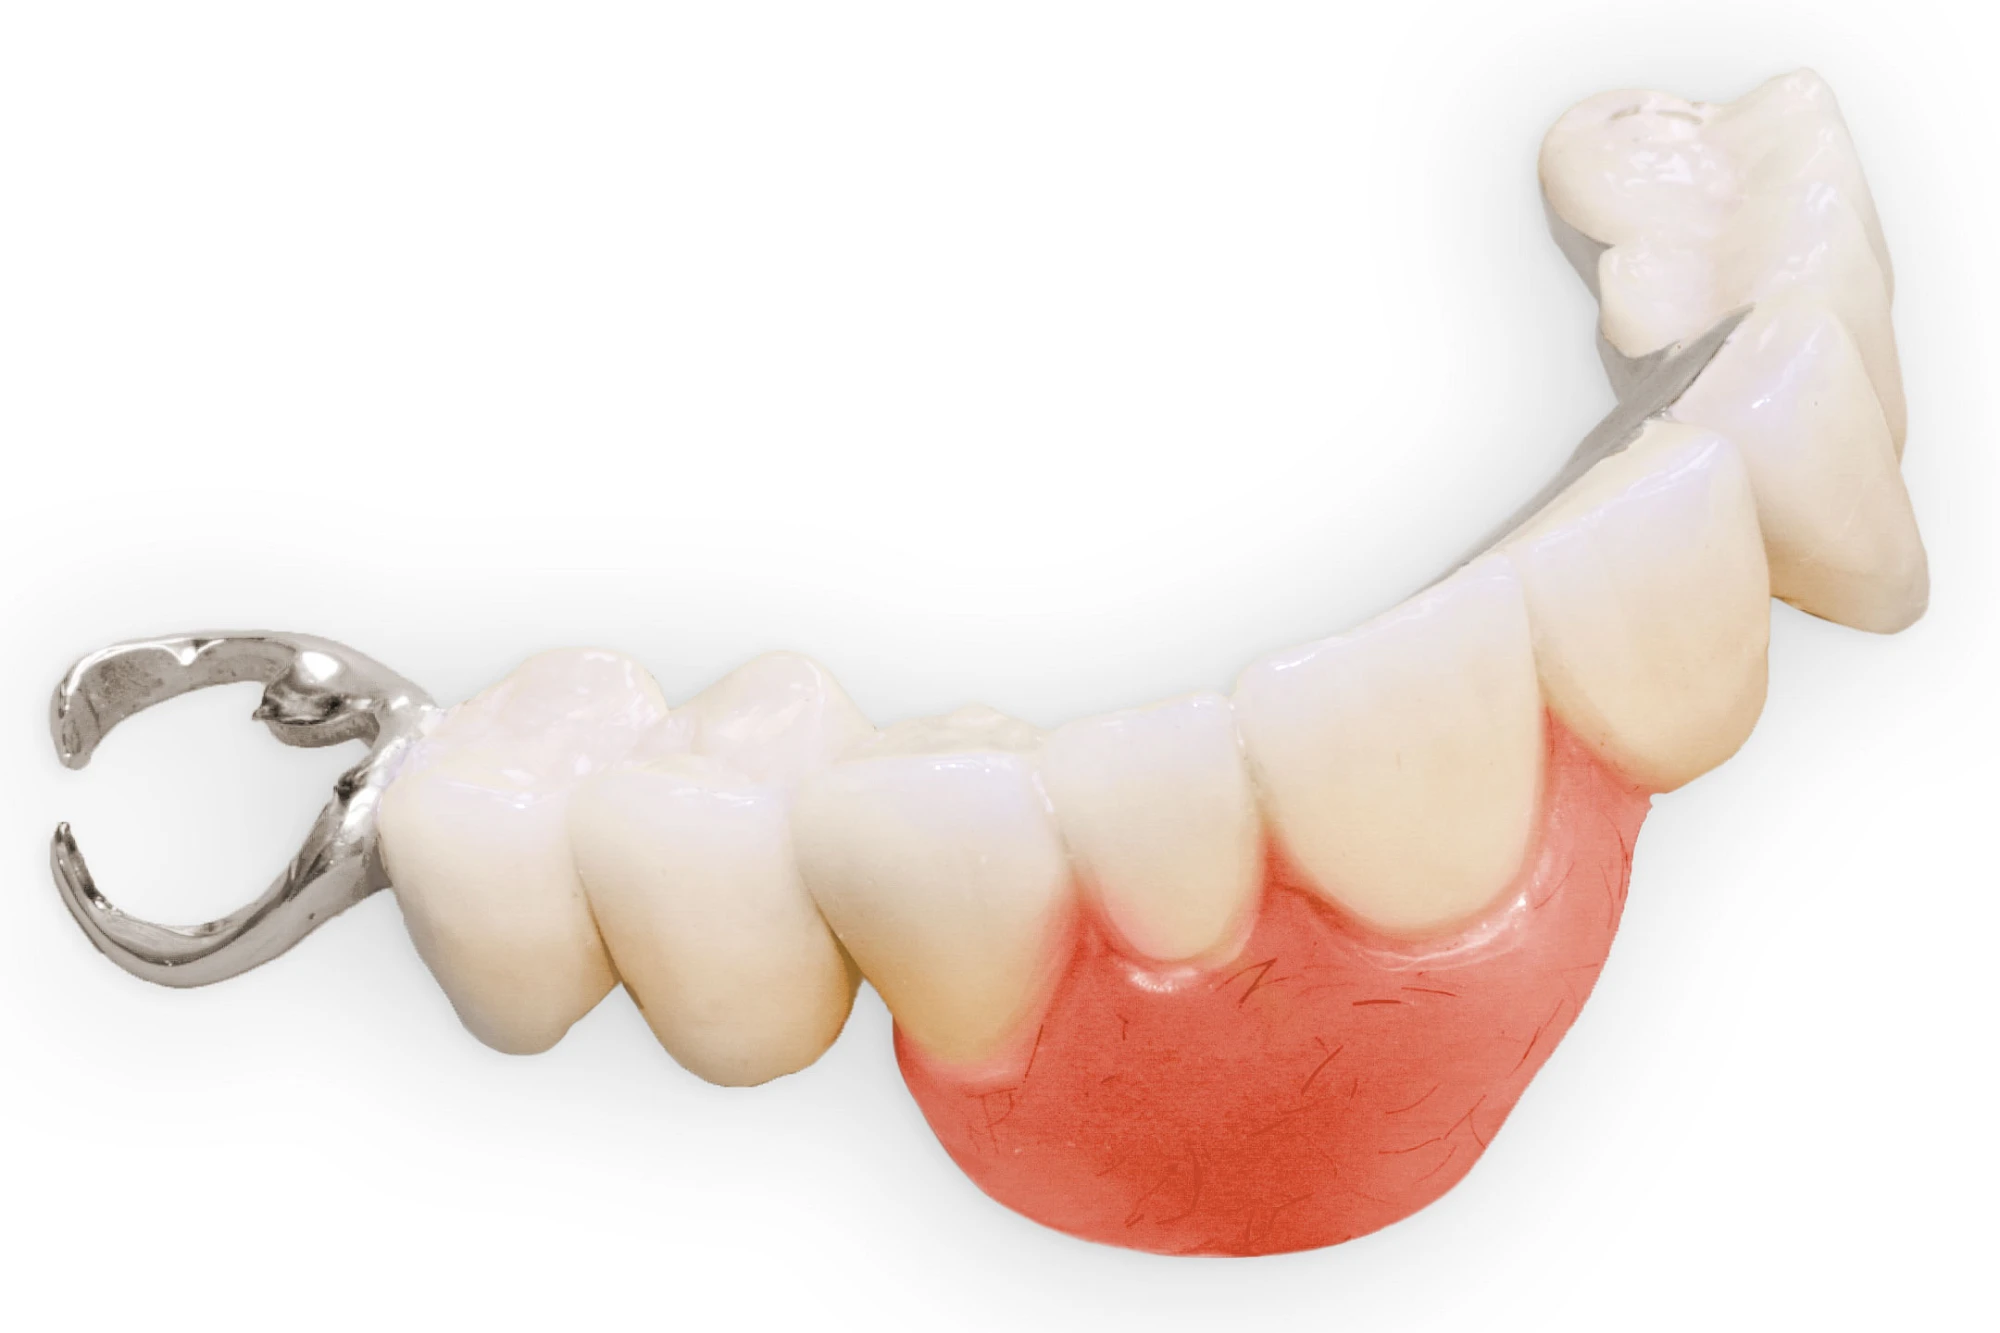

Gehen die Zähne verloren, baut häufig auch der Kieferknochen ab (Knochenschwund). Die Geschwindigkeit und das Ausmaß des Knochenschwundes ist von vielen Faktoren abhängig. Neben der genetischen Veranlagung spielen auch Überbelastungen in Folge, z. B. bei ständigem Knirschen oder Pressen, eine Rolle. Auch wenn Zahnprothesen Tag und Nacht getragen werden, kann die ständige Belastung der Schleimhäute und des Knochens den Knochenschwund beschleunigen.

Aber Achtung: Manche Menschen fühlen sich ohne Zahnprothesen unwohl. Zudem kann es passieren, dass Zahnprothesen (wenn noch eigene Zähne vorhanden sind) nicht mehr passen. Dies gilt vor allem dann, wenn diese Zahnprothesen nicht nur über Nacht, sondern für einen längeren Zeitraum nicht mehr getragen werden.

In jedem Fall sagen die Betroffenen, dass es sich ein paar Minuten komisch anfühlt, wenn sie die Zahnprothesen über Nacht aus dem Mund nehmen und dann morgens wieder einsetzen. Das ist normal und liegt daran, dass die Schleimhäute sich wieder regenerieren. Das ist gut für die Schleimhäute und Knochen im Bereich der Kiefer. Wir gehen ja auch nicht mit Schuhen ins Bett!

In seltenen Fällen schwindet nur der Knochen, aber nicht die bedeckenden Schleimhäute. In diesen Fällen spricht man von einem sogenannten "Schlotterkamm".

Auch wenn Zahnprothesen drücken, sollten vor allem Teilprothesen jeden Tag wenigstens für ein paar Minuten getragen werden, damit sich die eigenen Zähne nicht unbeabsichtigt verstellen und die Prothese weiter passt.